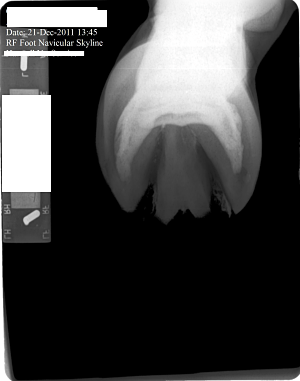

Posted on Friday, Jan 27, 2012 - 2:44 pm: The pastern joint doesn't appear to match the angle of the coffin joint or the fetlock joint...does it?What does this suggest? What else in these X-Rays would suggest 'trouble'? Mare is three and now in corrective shoes. Medial and Lateral balance was terrible. She is in a show barn and not worked a great deal and has little turn out. Thank you everyone.

Posted on Sunday, Jan 29, 2012 - 7:53 pm: Thanks Cheryl. It was late Friday when I posted, and I figured everyone would be off having a week end. Anyway, for what it's worth, I see the beginning possibly of side bone on the lateral side. I see the pastern joint angle does not match the angles of the fetlock and coffin joint. I cannot tell where the coffin joint is in relation to the coronary band. She has long under run heels and long toes. I don't know if the depth/shape of the collateral grooves tells me anything. The ski tip on the front of the coffin bone bothers me especially on a horse only 3. And is there a small bit or rotation down as well? I don't understand in the X-Ray why her sole appears to be bearing the weight and the hoof walls are off the ground. Is this really how she was prior to 'corrective' shoeing or is this X-Ray poorly taken or am I just poor at interpreting it. Or has her hoof mechanism sunk into the hoof capsule some? I do not have vet remarks for these X-Rays. |

Posted on Sunday, Jan 29, 2012 - 8:16 pm: left front The first X-Ray cut off the fetlock joint. This was not an editing error.The coffin joint looks uneven to me. Bigger space on the medial side. What does that mean? Nothing or something. I can't tell if this mare is built like a stack of playing cards or not(remember stacking cards like the wobbly Leaning tower of Pisa?). And how come the left lateral view the hoof wall is on the block but the right lateral view the hoof wall is off the block...is this an operator error or wonky foot? |

Posted on Tuesday, Jan 31, 2012 - 8:12 am: Hello Vicki,In general I avoid interpreting radiographs on the internet as the quality of the images here are not high enough to do a good job and the amount of time required to look at all aspects of the radiograph. I do invite members to put up radiographs and I will comment on any diagnosis made by the veterinarian who took the radiographs. That said I do think the RF foot in the front appears to have an overly long toe and corresponding toe flare and underrun heel. I don't see these issues in the L fore. The problem with assessing the conformational issues your bring forth is that technique and how the radiographs are taken can greatly effect the relationship between the bones and create false impressions. For instance all a horse has to do is stand a little forward over the foot and the normal pastern will not be aligned. The conformation issues you raise are best assessed looking that the horse while standing square and moving in a straight line than by a static set of radiographs. DrO |